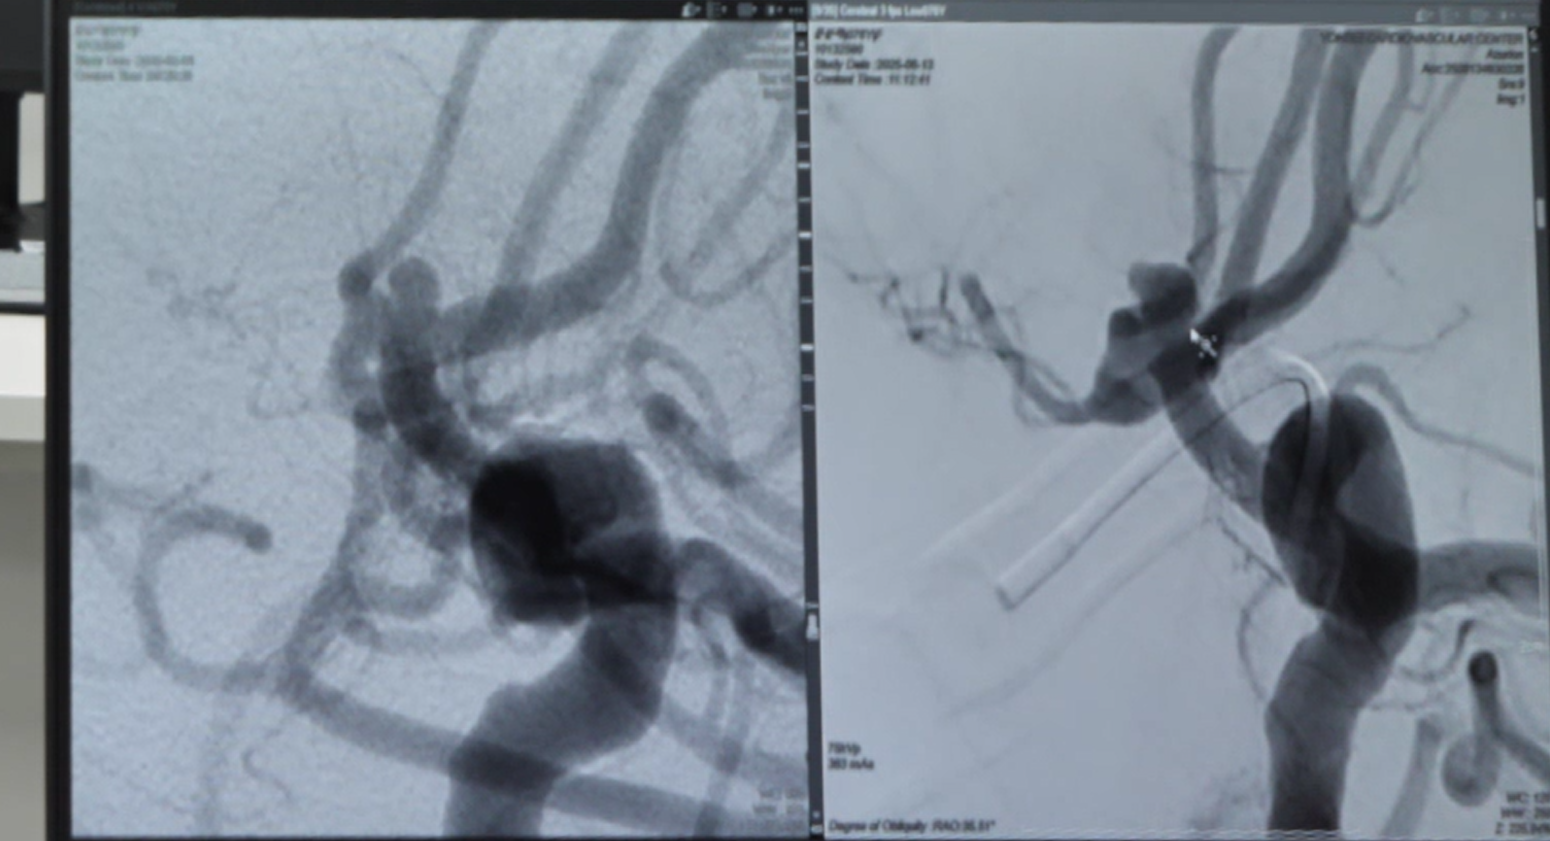

최근 뇌 동맥류 치료법은 눈부시게 발전했습니다. 과거에는 두개골을 열고 금속 클립으로 동맥류의 목 부분을 묶는 ‘클립 결찰술’과 혈관 안에서 코일을 삽입하는 ‘코일 색전술’이 주로 사용되었습니다.

지금은 더 다양한 선택지가 마련되어 환자의 상태에 맞는 맞춤형 치료가 가능합니다.

| 코일 색전술 | 동맥류 내부를 코일로 채워 혈류를 차단, 비파열 동맥류에 적합 | 파열 위험이 낮은 경우 |